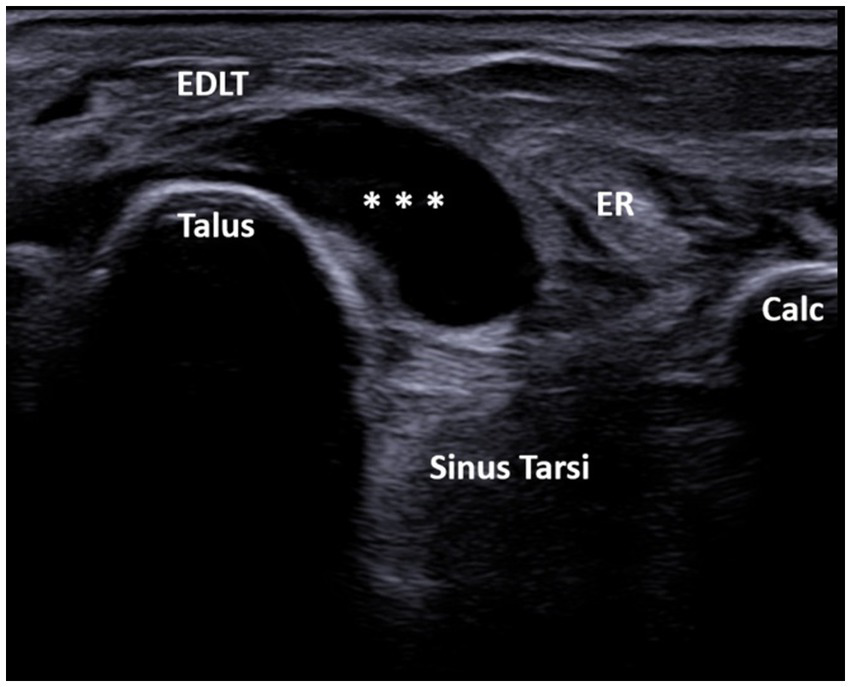

Figure 2

A 60-year-old patient with systemic sclerosis. Ultrasound image showing unilocular GB with the transducer positioned in the short axis of the foot (left side is medial). The transverse ultrasound image of the dorsolateral ankle shows an anechoic unilocular fluid collection (***) between the extensor digitorum longus tendon (EDLT) and the talus. ER, extensor retinaculum; Calc, calcaneus; and EDLT, extensor digitorum longus tendon.

A total of 608 patients underwent ultrasound examination for foot and/or ankle pain in our department from 1 July 2022 to 31 December 2023. Of these 608 patients, the search based on the previously cited keywords identified 76 patients who met the inclusion criteria. After reviewing the images of these patients, 13 were excluded for the following reasons: fluid collection was seen only deep within the sinus tarsi without spreading above the dorsolateral talar contour and beneath the EDLT (3 patients), tenosynovitis of the EDLT was diagnosed (6 patients), or no fluid was actually seen (4 patients). Thus, the final study group consisted of 63 patients with different primary rheumatic diagnoses (Table 1). Of these, the finding was unilateral in 48 patients and bilateral in 15 patients, resulting in a total of 78 bursae analyzed. Of the 63 patients, 45 (71%) were women and 18 (29%) were men. The average age of the patients was 61.7 years (range: 25–85 years). The right foot was affected in 55% (44/78) of the cases, and the left foot was affected in 45% (34/78) of the cases. The fluid collection extended from the sinus tarsi, along and beneath the inferior extensor retinaculum, reaching the space between the EDLT and the dorsolateral surface of the head of the talus. The large bursae also extended medially from this space. The bursae were predominantly unilocular (49/78) rather than multilocular (29/78). In all cases, the epicenter of the fluid collection was situated in the plane between the EDLT and the dorsolateral talar contour (Figure 2, Supplementary Video 1). When present, the second loculus was located medially to the main loculus and positioned over the talus (Figure 3). The majority of the fluid collections were clearly anechoic (69/78) (Figures 2, 4). In the remaining cases, internal hyperechoic foci were observed (Figure 5), making the content heteroechoic, and an internal septum was present in one case.

In our study, the GB was identified using MSUS as a structure distinct from both the tibiotalar and talonavicular joints, extending from the sinus tarsi along the inferior extensor retinaculum to the inferior surface of the EDLT, with varying sizes. The epicenter of the fluid collection, i.e., its thickest part, was always between the EDLT and the dorsolateral talus. In the longitudinal plane, the GB had an ellipsoid shape and was located between the EDL tendon and the talus (Figure 4). Its middle portion was the thickest, while the inferior and superior poles narrowed sharply. The margins of the bursa were well-defined in both the transverse and longitudinal planes, and it was clearly distinguishable from the EDLT, talonavicular joint, and tibiotalar joint.